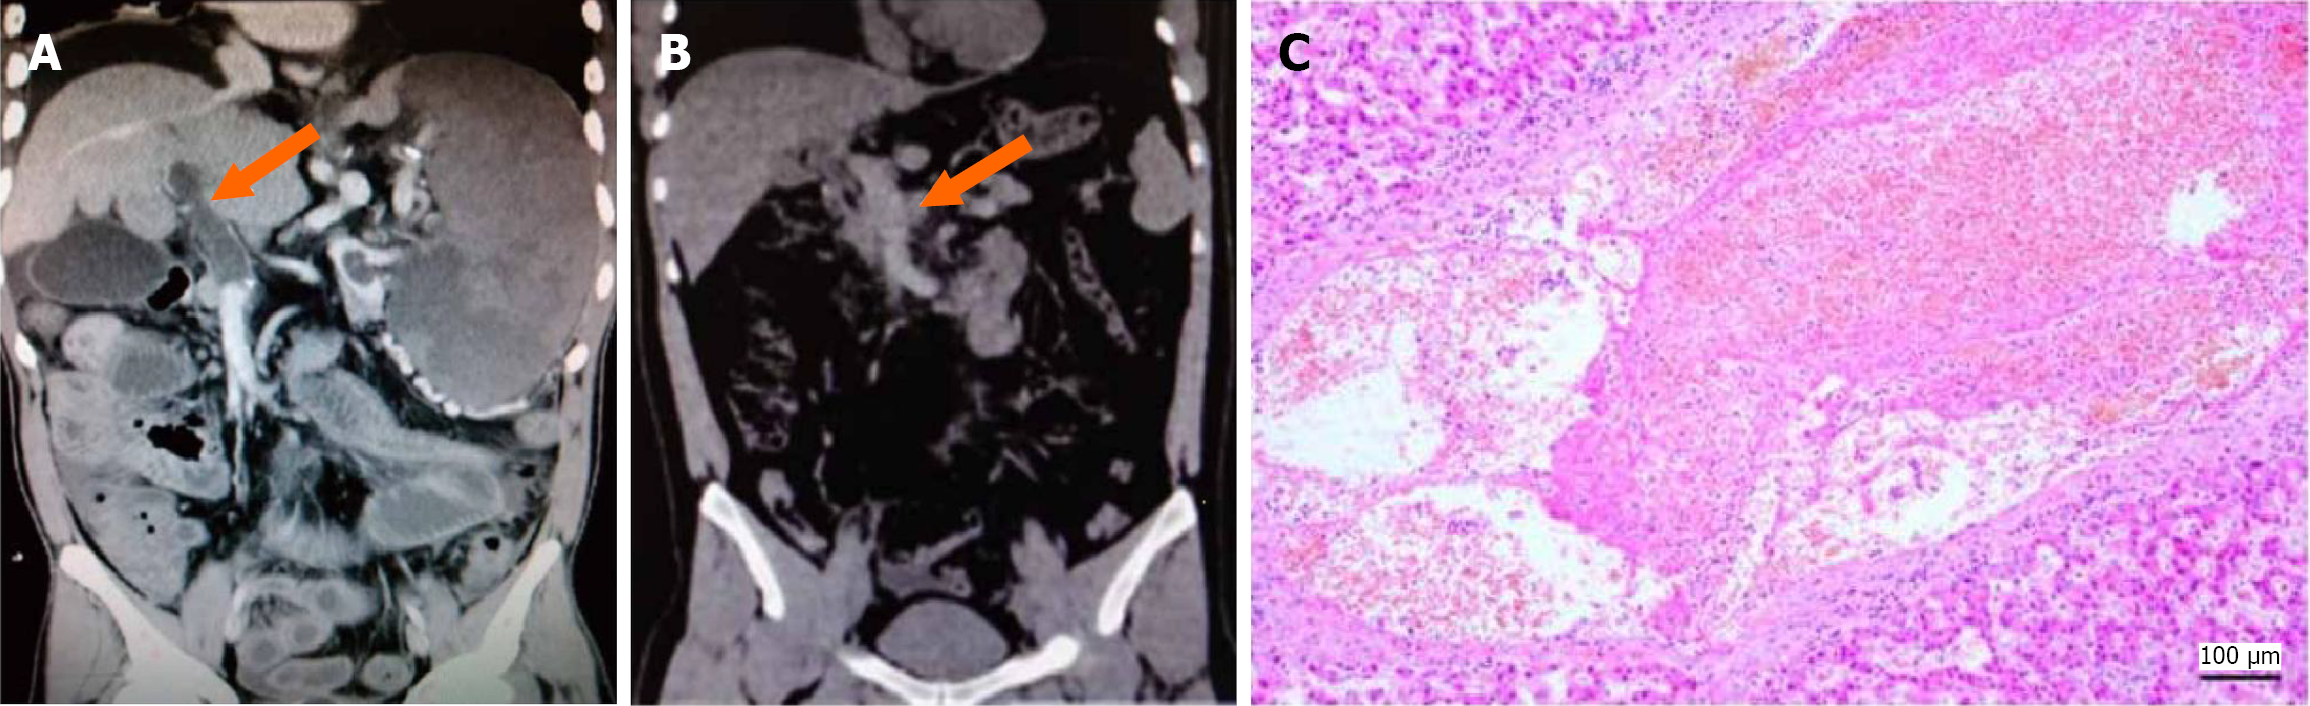

Acute PVT: In 46 patients (26.9%), the primary enhanced CT features included PVT that matched the vascular anatomy with very low-density shadows, uniform density (CT value: 39.98 ± 5.92 HU), no or minimal collateral vessel formation, and no thickening of the vessel wall (Figure 2A). In 4 patients, plain CT scans revealed that a small number of intrava

Acute PVT was present in 27 patients (19 underwent TIPS; 7 underwent percutaneous transhepatic portal vein access; 1 underwent liver transplantation). Pathologically, these thrombus samples were primarily composed of platelets and red blood cells, with normal vascular walls. Figure 2C shows a HE stained section demonstrating aggregates of red blood cells and a vascular wall of normal thickness.